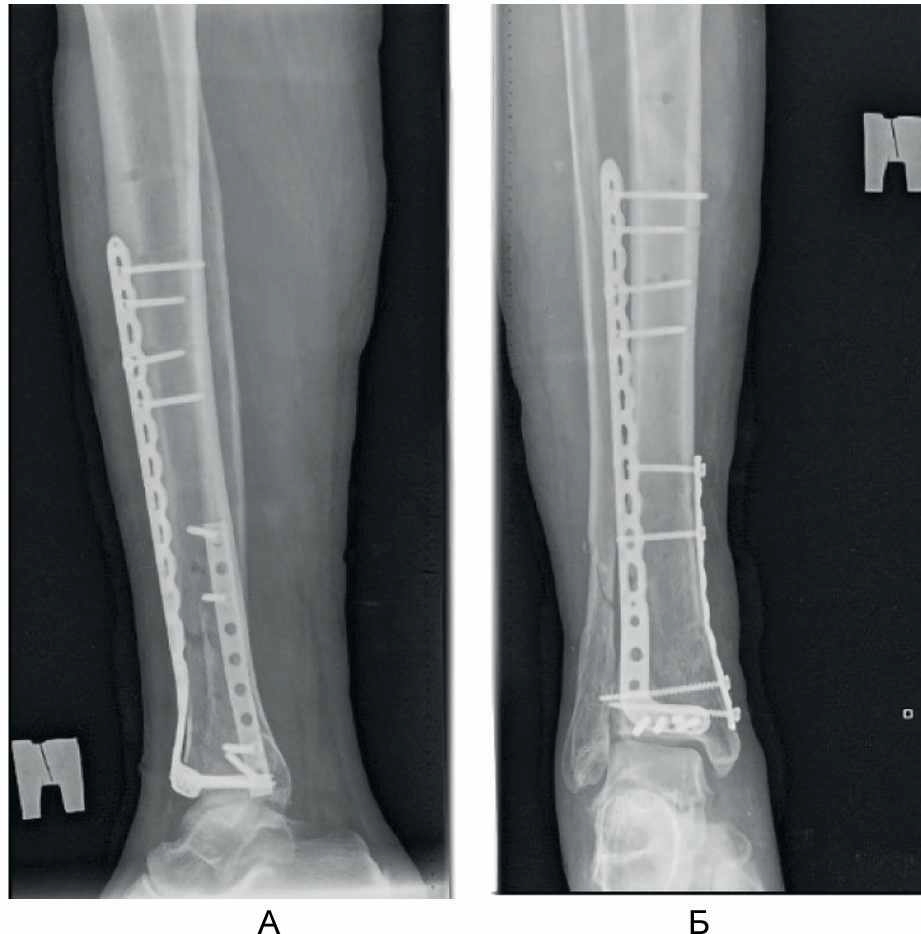

Положение отломков и имплантатов в ходе операции контролировали интраоперационной рентгеноскопией при помощи рентгеновского электронно-оптического преобразователя. Рентгенологический результат операции представлен на рис. 6.

Рис. 6. Рентгенограммы в боковой (А) и прямой (Б) проекциях после выполнения малоинвазивного накостного остеосинтеза нижней 1/3 большеберцовой кости.

Пациент осмотрен через 3 мес после операции. Он ходит с частичной опорой на оперированную конечность с тростью. Болевой синдром отсутствует. Тыльное сгибание и разгибание голеностопного сустава – в объеме 90–130°, функциональный результат по шкалам AOFAS и Neer [16, 21] составил 71 и 76 баллов соответственно (рис. 7).

Рис. 7. Результат оперативного лечения через 3 мес после вмешательства.

Руководствуясь изложенными соображениями, при предоперационном планировании остеосинтеза у нашего пациента Б., 66 лет, с переломом в области метаэпифиза правой большеберцовой кости и нижней трети диафиза малоберцовой кости мы постарались решить проблему латеральной стабильности с помощью установки опорной переднелатеральной пластины на большеберцовую кость, восстановив ее длину с помощью закрытой тракции в аппарате наружной фиксации (и этот момент мы считаем крайне важным, так как первичное восстановление осевых взаимоотношений и сохранение их в течении дооперационного периода, безусловно, облегчает репозиционные маневры в ходе окончательного остеосинтеза), с последующей установкой пластин через мини-доступы. Фиксация же малоберцовой кости из отдельных доступов в данном случае не потребовалась, так как цель ее остеосинтеза – устранение вальгусной деформации и латеральная стабильность – была решена остеосинтезом самой большеберцовой кости. Правомерность выбранной нами тактики в случае у нашего пациента была доказана клиническим и рентгенологическим сращением перелома большеберцовой кости, отсутствием при этом вторичного смещения отломков и хорошим функциональным результатом.

Контрольные рентгенограммы в прямой (А) и боковой (Б) проекции – определяется сращение перелома; В–Д – функциональный результат лечения.